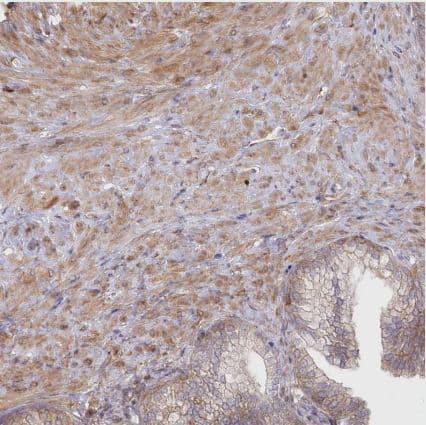

Immunohistochemistry-Paraffin: SH3PXD2B Antibody [NBP1-93965] - Staining of human prostate shows moderate cytoplasmic positivity in smooth muscle cells.

Staining of human prostate shows moderate cytoplasmic positivity in smooth muscle cells.